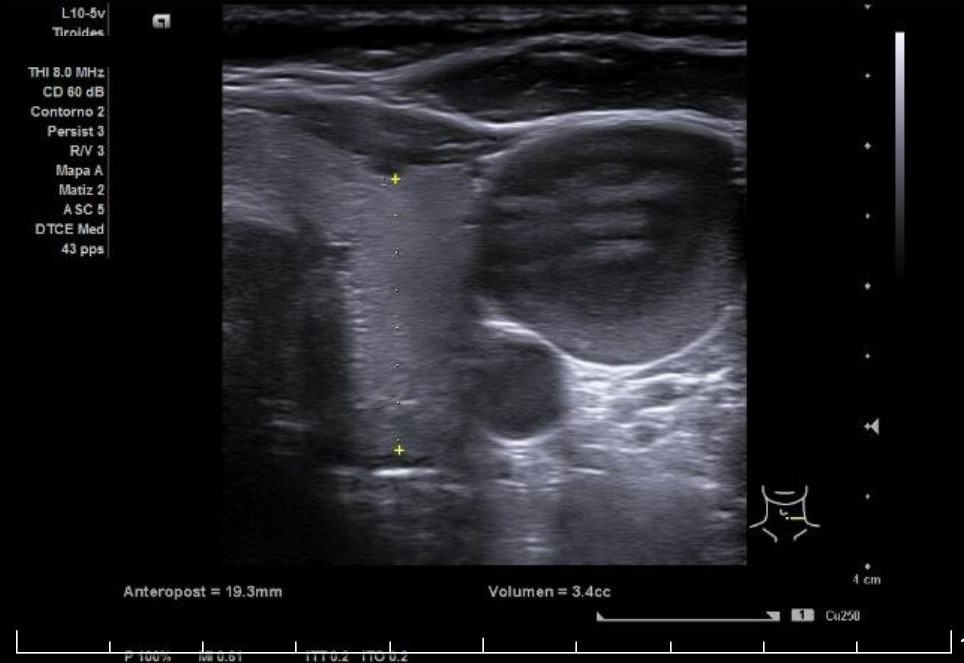

Paciente mujer de 63 años con antecedente personal de tiroiditis de Hashimoto y aumento de la grasa peritiroidea derecha que acude a consulta de su médico de familia por notarse aumento de volumen cervical anterior derecho de alrededor de una semana de evolución, negando dolor u otra clínica. A la exploración se palpa bocio ya conocido, con aumento de volumen cervical anterior derecho respecto de izquierdo, sin distinguir masa clara a la palpación. Es por la falta de claridad en la palpación que se decide realizar ecografía exploratoria durante el mismo acto clínico.

Se aprecia un tiroides de características ecográficas compatibles con tiroiditis, sin cambios respecto a ecografía previa, al igual que la grasa peritiroidea derecha, pero de manera incidental se observa un aumento del calibre fusiforme de la yugular externa derecha con respecto a la izquierda, con flujo vascular reducido.